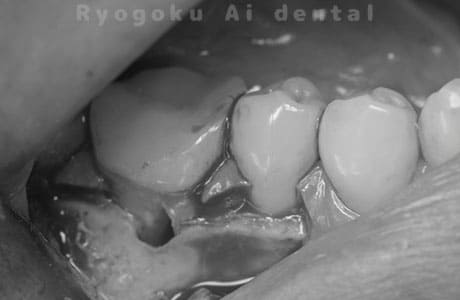

Case04

-

- 原因

- 右下6番パーフォレーション

- 治療内容

- パーフォレーションリペア

- 治療費用

- ¥66,000

右下奥歯が他院で行った治療後、腫れが引かないとのことでご来院された患者様です。近心根の遠心壁にパーフォレーションを認めたため、外科的にパーフォレーション部の修復を行いました。経過良好です。

<リスク・副作用>

手術後は痛み、腫れ、痺れ、青あざなどの副作用が生じます。痛みは痛み止めを処方しますが、腫れ、青あざは1週間程度生じる場合があります。また、部位によっては神経の走行が複雑で、痺れが残り、長期的にお薬を処方する場合があります。